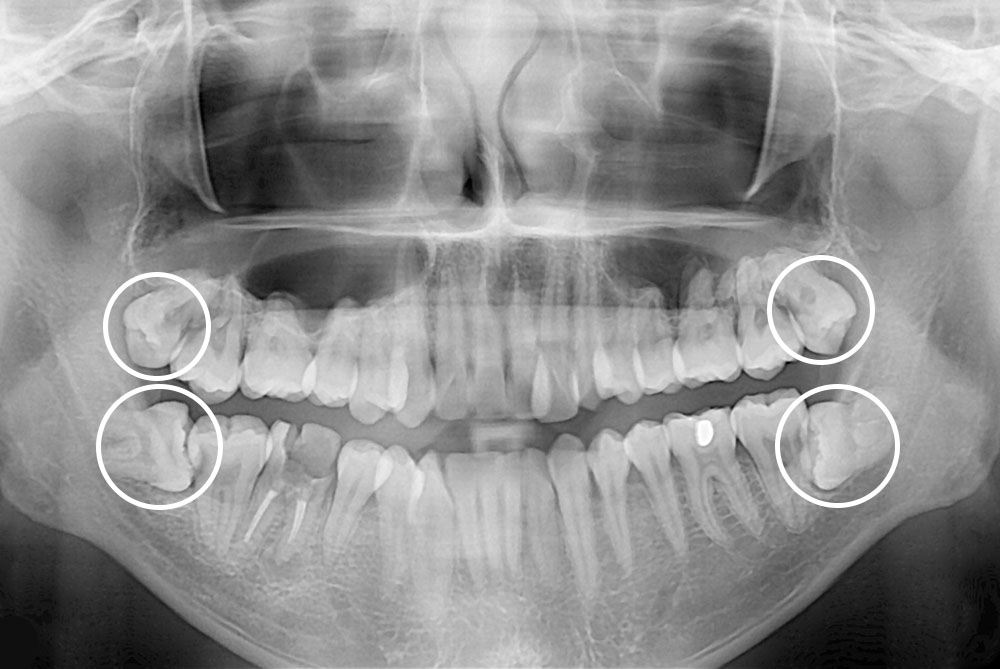

[사랑니] 매복 사랑니 발치

치료후 : 2020-07-08

세종치과는 구강악안면외과학 박사이신 원장님이 발치하는 치과입니다.